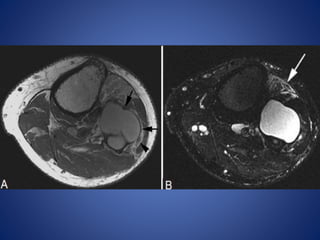

• #17 Pes anserine bursitis. A 30-year-old male with medial knee pain. (A) Axial T2W and (B) sagittal T2W fat-saturated images demonstrate fluid signal (arrows) adjacent to the insertion of the pes anserine tendons

• #19 Medial collateral ligament bursitis. A 56-year-old man with medial knee mass and pain. Coronal T2W fat-saturated image shows an oblong heterogeneous cystic mass (arrow) adjacent to the medial collateral ligament (arrowhead)

• #21 Gastrocnemius ganglion. A 45-year-old male with knee pain. Sagittal PDW image (A) demonstrates lobulated lesion (arrows) at insertion of medial head of gastrocnemius that is hyperintense on sagittal (B) and coronal (C) T2W fat-saturated images

• #22 Popliteus ganglion. A 34-year-old woman with knee pain. (A) Axial and (B) sagittal T2W fat-saturated images show a cystic lesion (arrow) in the popliteus tendon sheath